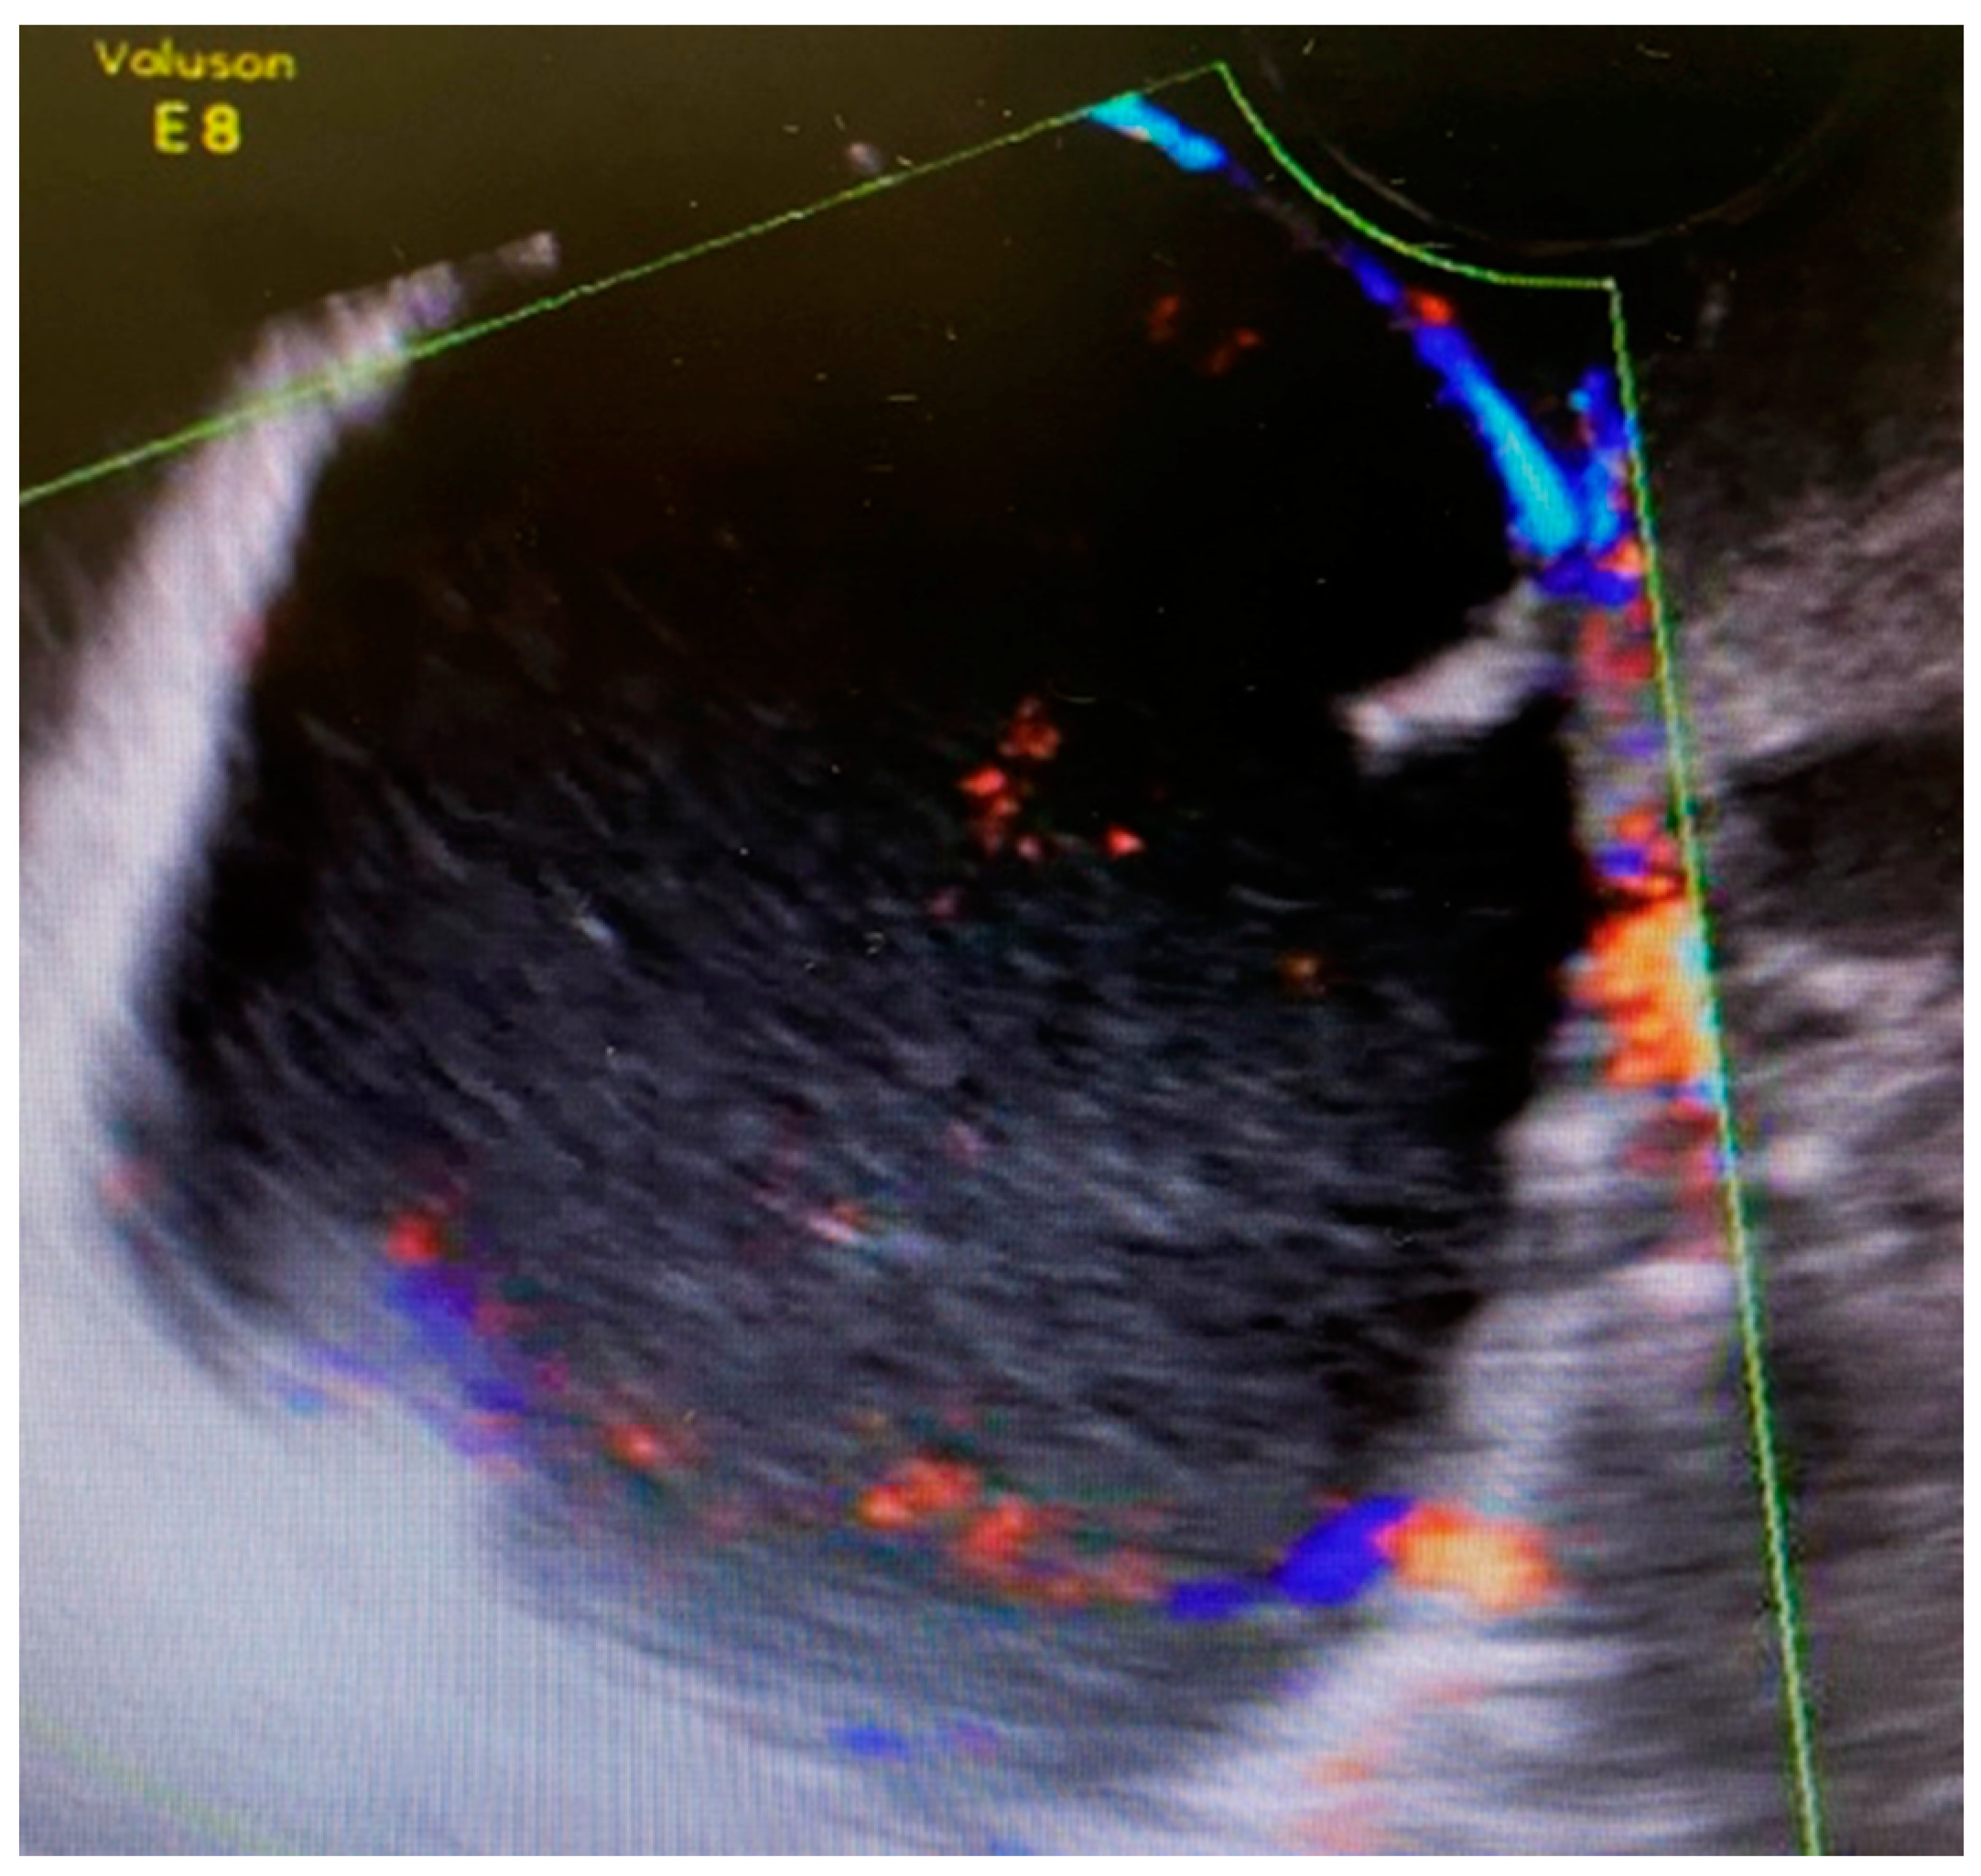

The first 12-week ultrasound showed 66 mm × 48 mm cysts between the bladder and the cervix with peripheral vascularization, and another left paracervical cystic and heterogeneous lesion of 39 mm × 26 mm size (Figure 1). A follow-up visit was indicated requiring close monitoring.

Figure 1. Ultrasound scan compatible with complex cystic formation.